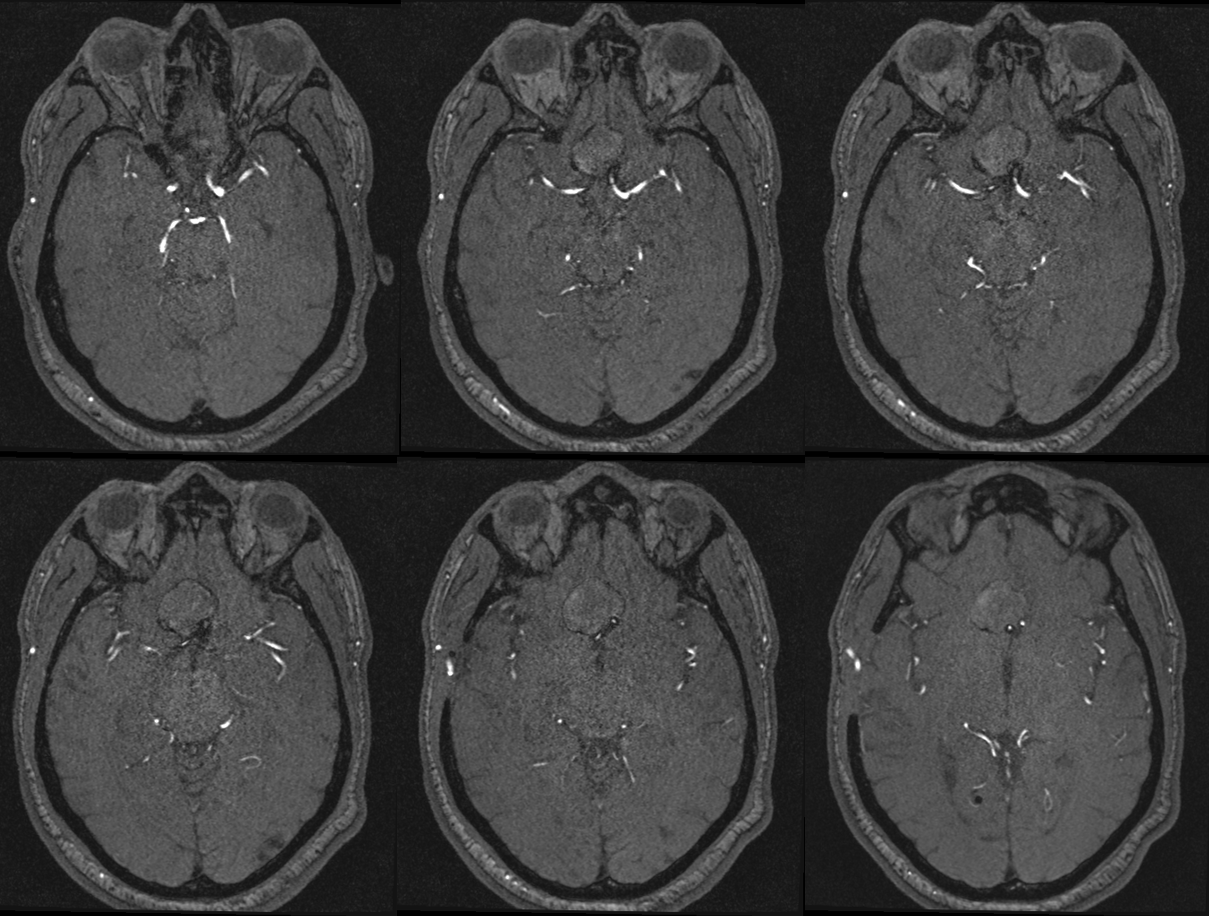

Spin

A better unsubtracted spin

1 mo later — open portion is larger despite same medication regimen

Bypass working even better

PCOM working correspondingly less. Ophthalmic no longer needed

Bilateral CBCT Injections. A big bonus — the ACA-ACA bypass now seems to be patent! Cant see that from 2D images really at this stage. We did not realise this at first but became clear later